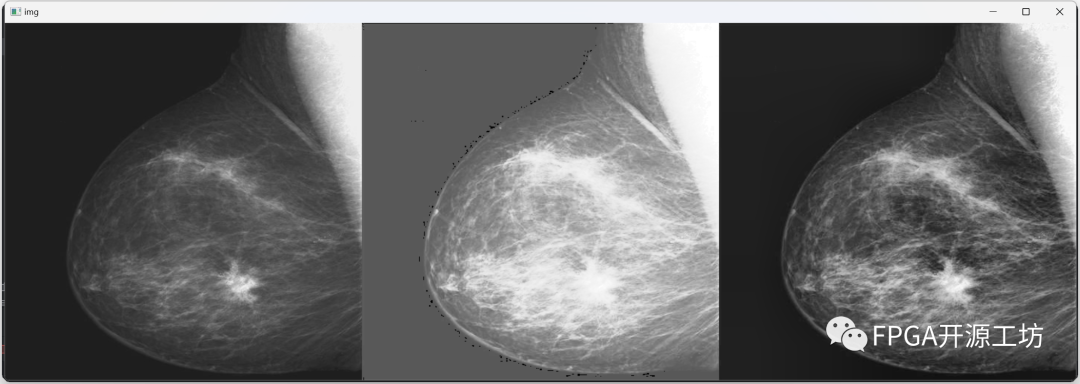

eebf8ffa-a923-11ee-8b88-92fbcf53809c.png

eee00186-a923-11ee-8b88-92fbcf53809c.png

最左侧为原图,中间为直方图均衡化后的结果,最右侧为CLAHE算法的效果。

从视觉效果上来看,CLAHE算法的效果最为明显。